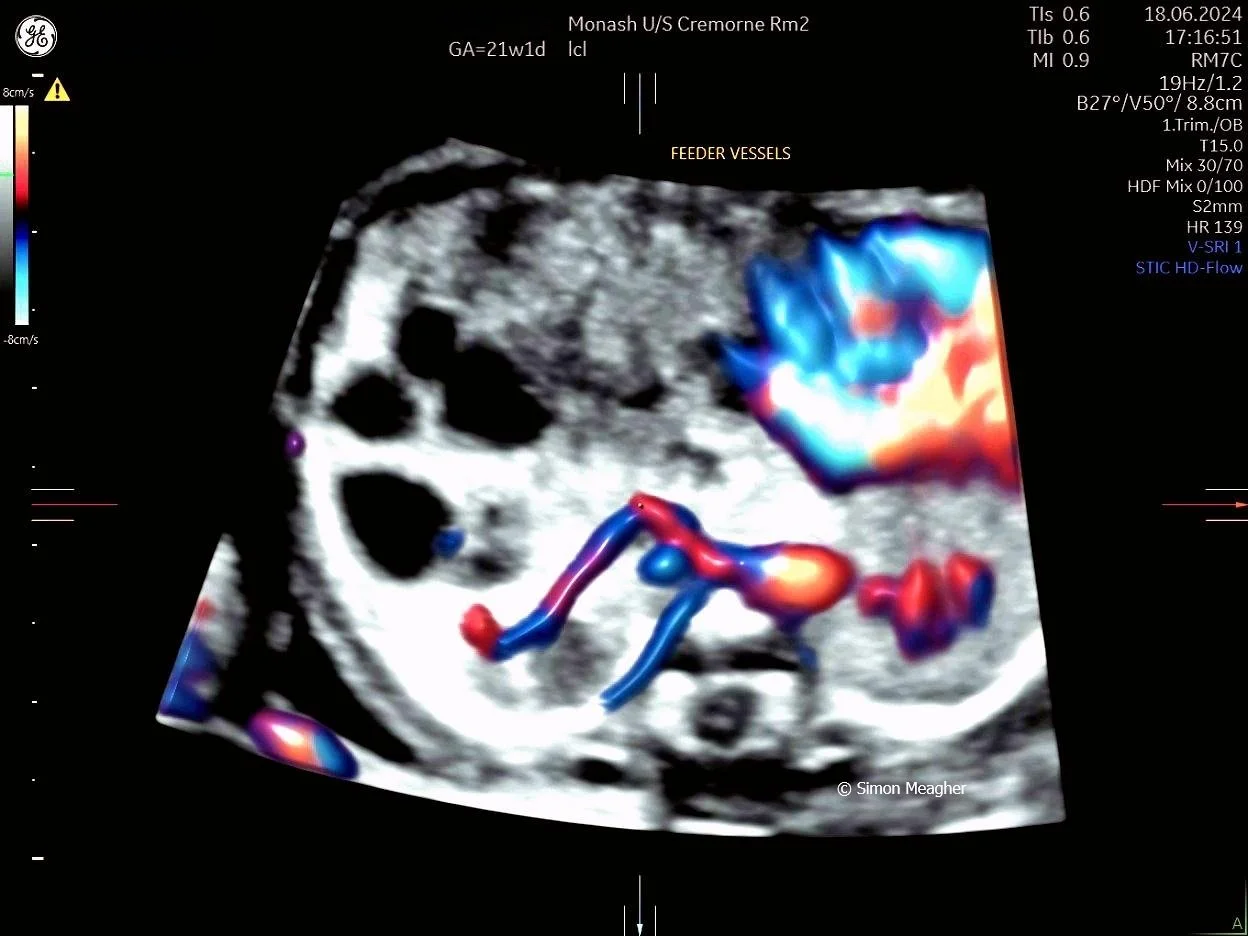

Join Professor Simon Meagher and leading experts for an intensive masterclass designed to transform your clinical practice.

This high-impact, one-day event delivers live scanning demonstrations, real-world case studies, and cutting-edge techniques across all trimesters.